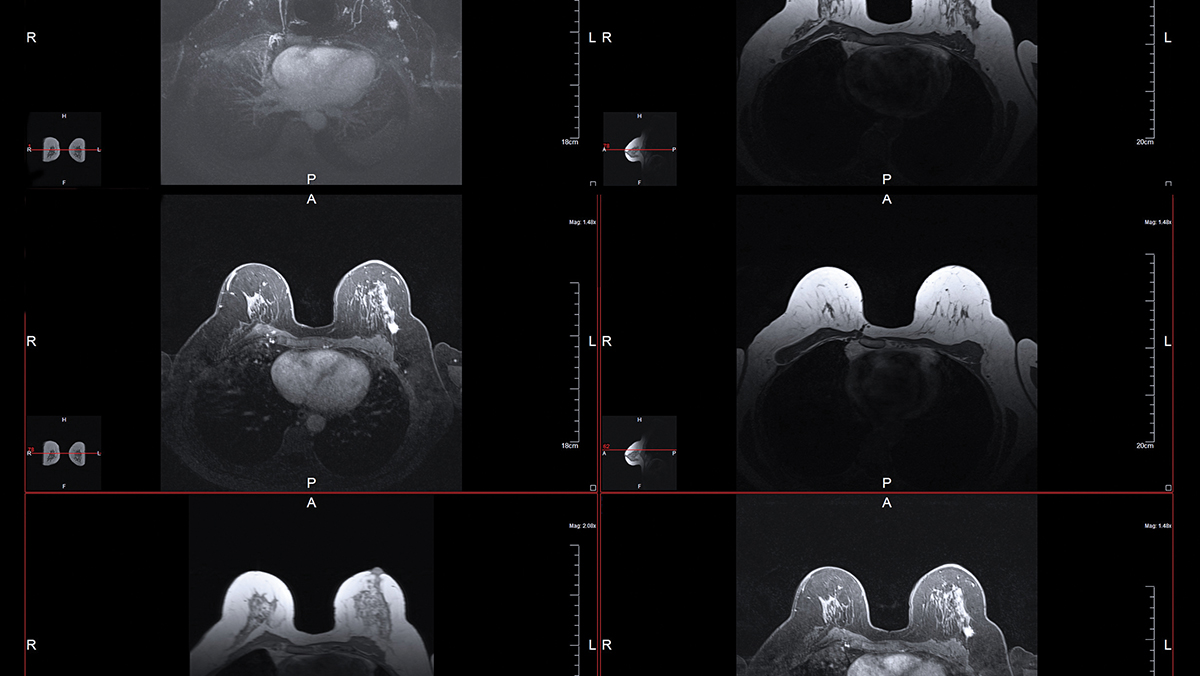

Refining Stereotactic Body Radiation Therapy for Breast Cancer

- Asal Rahimi, M.D.

October 2, 2020